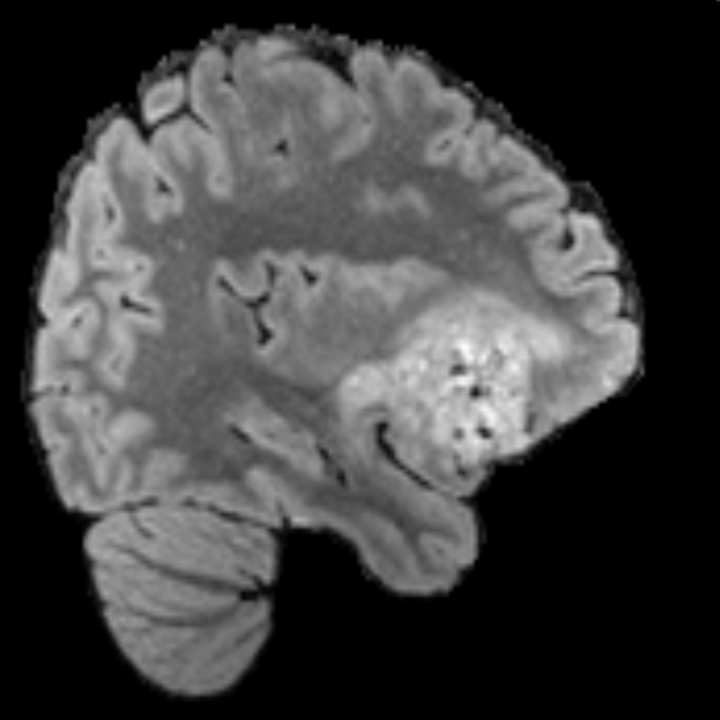

To see when and how X-Diffusion fails, we conducted an experiment on healthy brains (no tumour) using IXI dataset, by running an X-diffusion trained on BRATS brain tumor dataset. Our X-Diffusion achieved a PSNR of 35.86 dB on the IXI dataset despite being trained on the BRATS dataset. We then ran the tumour segmenter on the set of 582 healthy scans and corresponding generated MRIs. The segmenter predicted tumours in 9.9% of the real healthy brains and in 11.3% of the generated brain MRIs. Some of these tumor hallucination examples fron X-Diffusion generation are shown in Figure 10.

| Hallucination | Reference | Hallucination | Reference | Failure | Reference |

On the test set with human ground-truth annotations (), the brain volumes generated from single slice input preserve the volume of the different tumour components (paired t-test, for all 3 classes) (see Table I). The real MRI Dice scores are put for reference to our generated MRIs. X-Diffusion outperforms baselines TPDM [39] and ScoreMRI [19] in tumour preservation (see Table I and Figure III). We ran experiments comparing the tumour segmentation Dice Score varying X-Diffusion configurations. The multi-slice input X-Diffusion achieves marginally better Dice Score than the single slice input model (83.47 83.09). We also ran experiments with slice input used for volume reconstruction intersecting or not with tumour. We observe on average a drop of 6% Dice Score (see Table I). Further away from the tumour the input slice for volume reconstruction is selected, we observe a linear decrease in tumour segmentation Dice Score with lowest value of 77.21 Dice Score (see Figure VI).

This shows how the generated MRIs indeed preserve the tumour information and can act as an affordable and informative pseudo-MRI, before conducting an actual costly MRI examination in hospitals. Given that our model has been trained on brain scans all with tumours, we expect to see hallucinations of tumours in healthy scans. We report two cases of failure of our model in Figure VII. Hallucinations of tumours on healthy samples represent 2% of the test set.